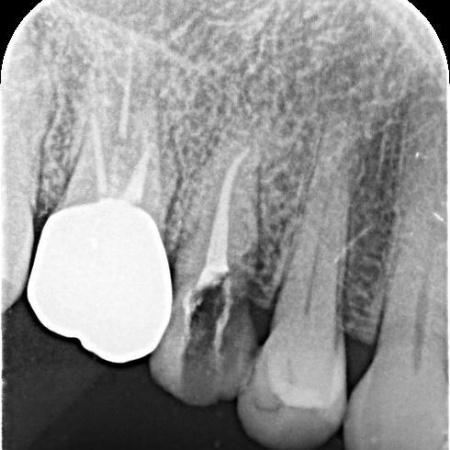

| 診断 | レントゲン撮影をして詳しく拝見したところ、右上奥歯の頭部分「歯冠」が縦に割れる「歯冠の垂直破折」が確認できました。 割れ目が深い場合は、歯の温存が困難です。 今回の症例では、症状や割れ方に応じて治療方針を慎重に判断する必要があると診断しました。 |

1:細菌感染した神経を取り除いてから薬を詰める「根管治療」 2:歯を長く使えるように土台をたてる「支台築造」 3:被せ物による「補綴修復」 以上のメリットとデメリットを丁寧にお伝えし、治療に同意いただきました。 まず、割れている部分をしっかりと確認し、必要な部分を除去してから根管治療を行います。 最後に、完成した被せ物を装着し、噛み合わせや見た目に問題がないことを確認して、治療を終了しています。 なお、患者様の下の歯の治療についてはこちら:https://dr-kaiya.com/blog/20260312-2/ |

治療中